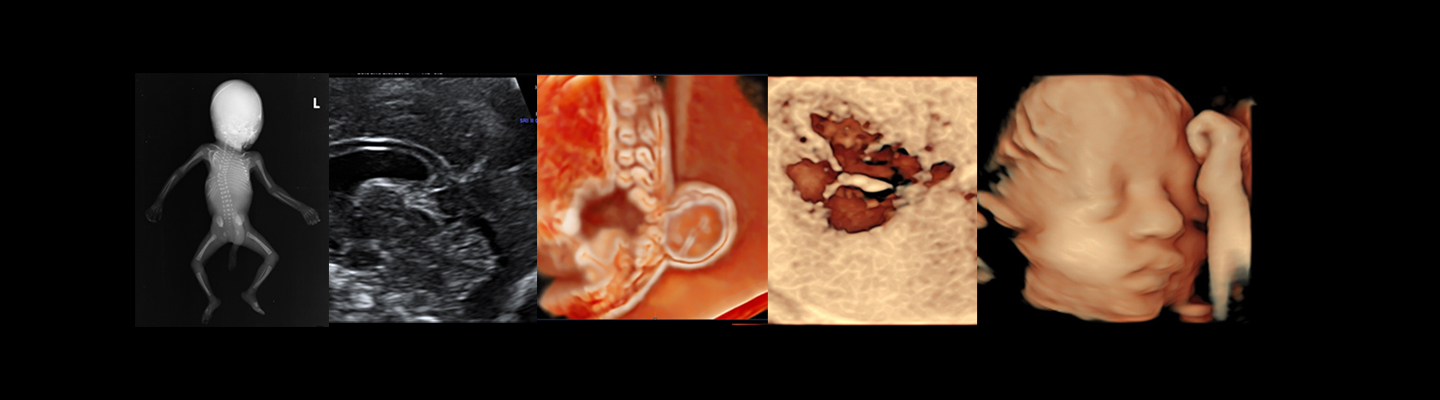

Fetal medicine is about the study and treatment of the fetus within the womb. This is a rapidly evolving specialty wherein the fetus is treated as a patient either jointly or separately treated from the mother depending on the clinical indications. The diagnosis and management of fetus, therefore, requires expertise to be developed outside the traditional boundaries of obstetrics and neonatal specialty. It is also important to have a broad knowledge of understanding the fetus and its relation to the maternal environment to optimize management.

This unique fellowship training programme curriculum is designed to provide structured training in a university hospital as a sub specialist - along with the benefits of being trained at a tertiary referral centre for fetal diagnosis and therapy, by dedicated faculty specifically trained in fetal medicine.